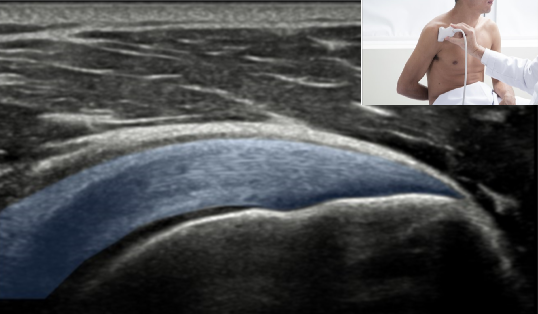

QUAL A ESTRUTURA ASSINALADA NA FIGURA?

TENDÃO DO INFRAESPINHAL